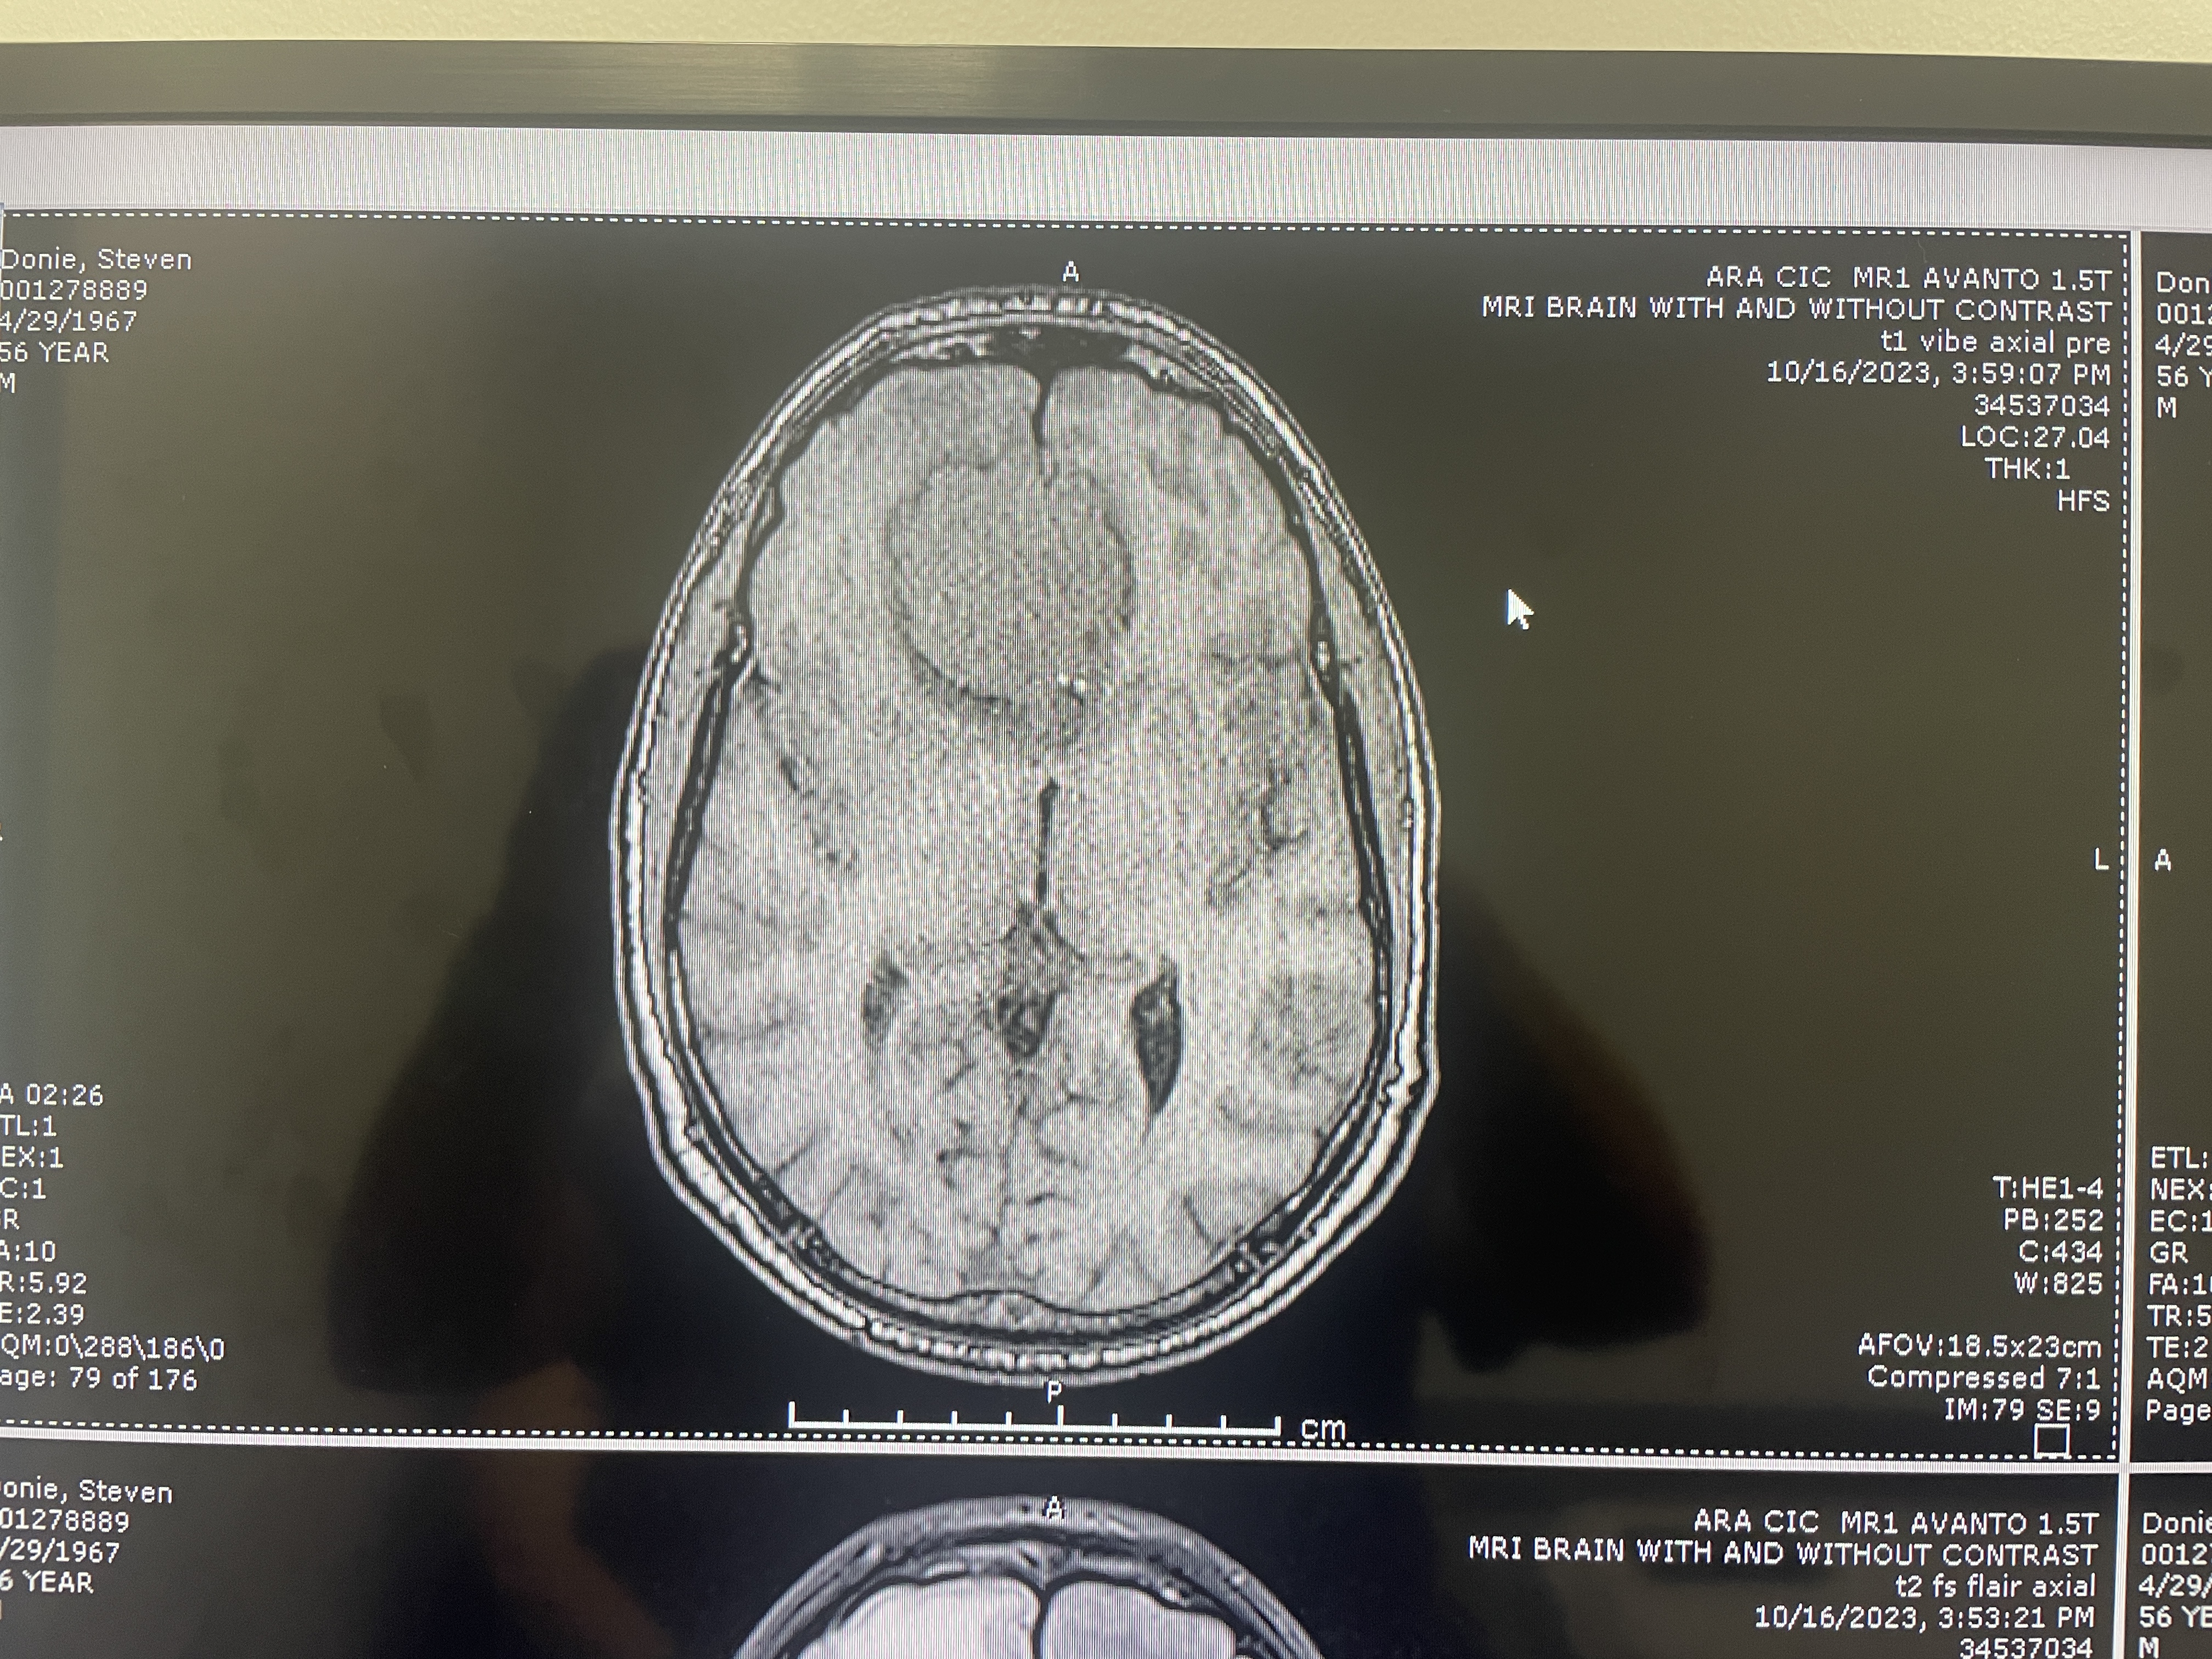

Another MRI top view